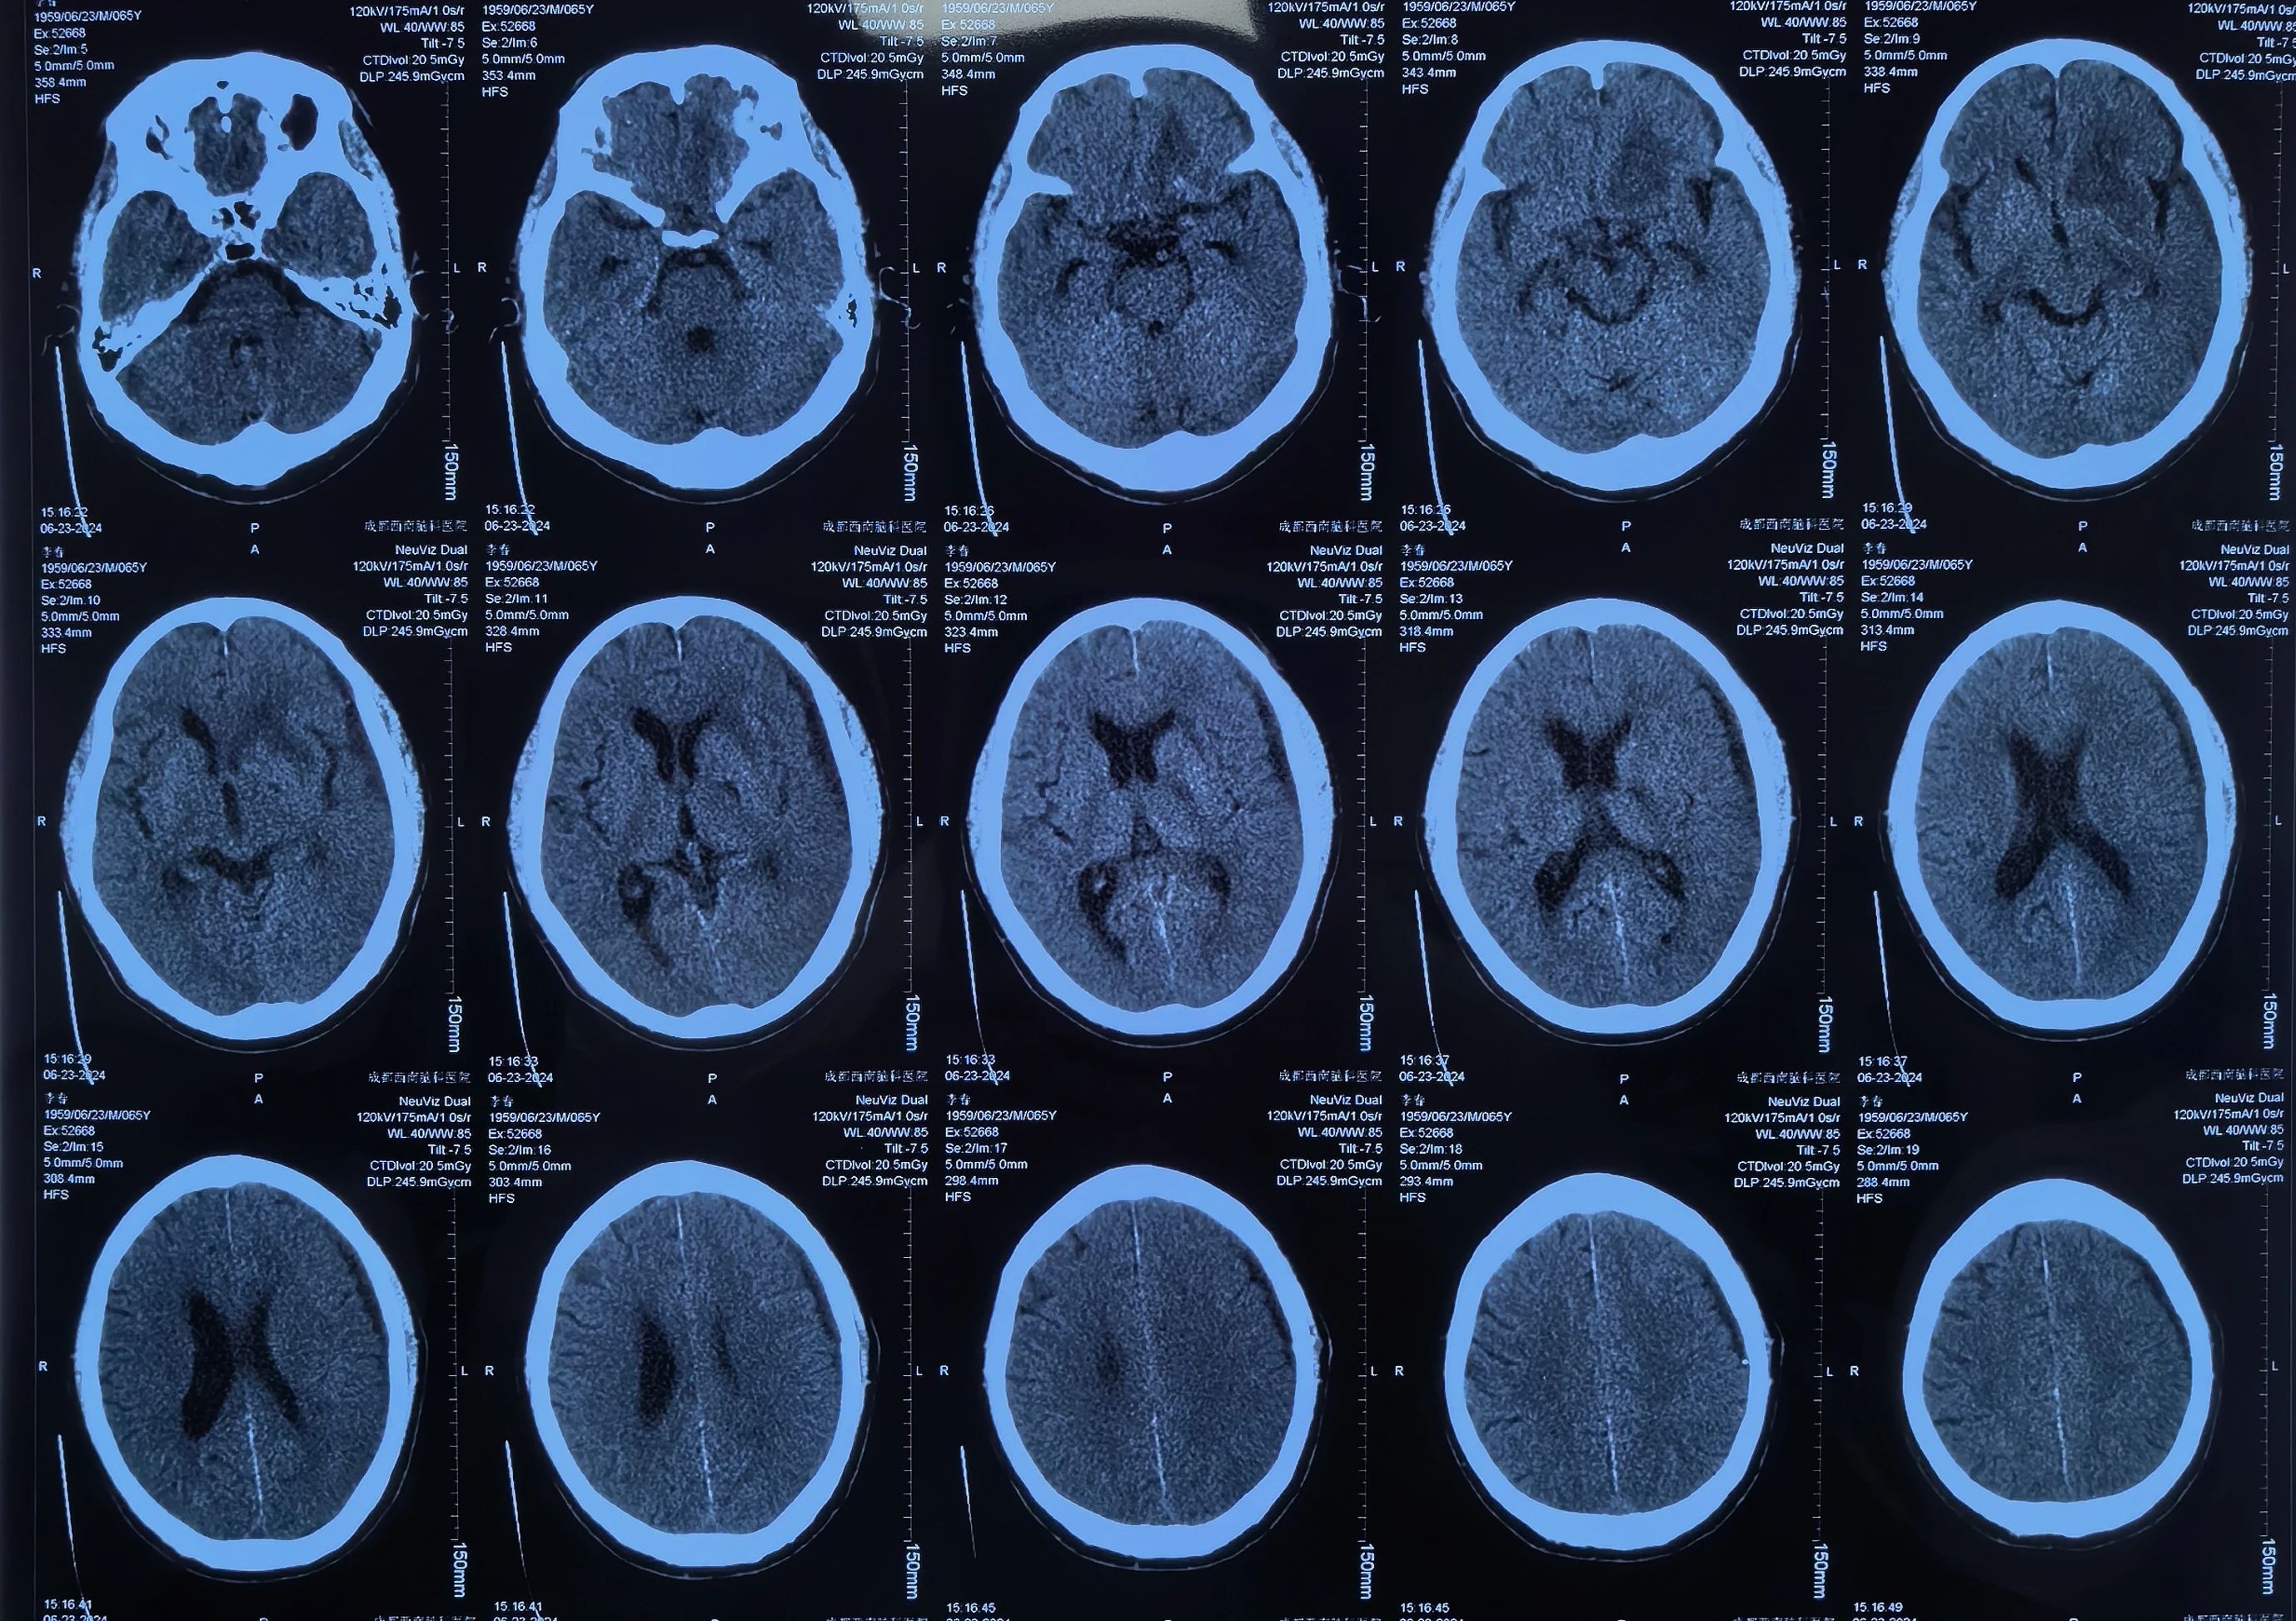

李先生有高血压病史3+年,最高血压166/88mmHg,血压控制一般。10+天前突然出现意识丧失,立即就诊当地医院。李先生送医途中就恢复了意识,但全头部爆炸样胀痛,诊断为脑出血、硬膜下血肿、蛛网膜下腔出血,大脑前动脉中度狭窄,颈内及大脑中动脉均发现动脉瘤。

因当地医院对症治疗一周效果不佳,为求进一步治疗,家人带着李先生辗转来到我院。经左剑主任与李积荣主任联合会诊,认为李先生目前的头痛主要与脑内血肿引起的脑水肿及硬膜下血肿引起的颅高压有关。因患者有多发颅内动脉瘤,最终决定局麻下采用“颅内血肿微创清除技术”清除硬膜下血肿。

颅内血肿微创清除技术是目前治疗高血压性脑出血最简单、最安全、最有效的方法。利用颅脑CT片或CT下进行三维立体定位,采用一次性使用颅内血肿微创穿刺针进行穿刺抽吸,外径只有3毫米,针钻一体,设计合理,操作简便,易固定,密闭性好,创伤小,不易感染,抽吸无盲区,相比开颅手术费用低廉,可以快速清除颅内血肿,缓解颅内压力,大大地降低了患者的死残率,提高了患者的生存质量。

术后李先生自觉头痛明显减轻,术后第三天复查头颅CT提示:硬膜下血肿基本清除,脑移位恢复正常。